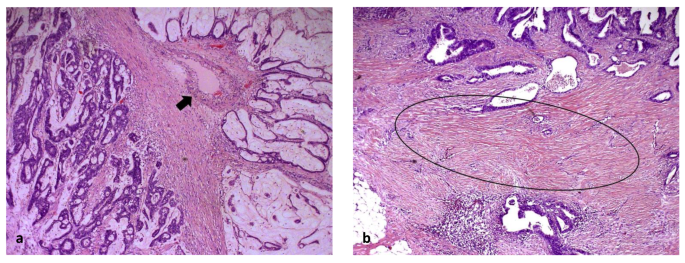

Mucinous adenocarcinomas

In mucinous cancers, it can be very difficult to estimate the TSR correctly. The mucus is allowed to be present in the field of vision, but has to be visually ignored from scoring (Table 2, Fig. 2a, Supplementary fig. 1). It may also be possible to determine the TSR in the non-mucinous area of a mucinous tumor’s deepest penetration of the bowel wall.

Fig. 2

figure 2

Examples of infiltration of a mucinous colon carcinoma (a) and inflammatory cells (b), which both meet the criteria for scoring. For the mucinous colon carcinoma, the mucus has to be ignored for scoring. Fields of vision with necrotic tissue (c) and smooth muscle tissue (d) do not meet the scoring criteria and should not be considered for scoring (Images displaying the microscopic view, all images × 100 magnification)

Infiltration with inflammatory cells

Heavy inflammation is often encountered within the stromal component in the tumor microenvironment of colon adenocarcinomas, and can be included in the TSR scoring as part of the stroma. However, lymphoid follicles may represent an integrated part of the “native” histology of the large bowel, and thus may not constitute a response to the expanding epithelial tumor within the tumor microenvironment. Thus, we recommend areas with lymphocytic follicles/aggregates to be avoided or else visually ignored from scoring (Fig. 2b).

Necrotic tissue

Necrotic tissue or areas with pure neutrophilic inflammation, which may indicate necrosis, should be left out of the microscopic scoring field. If this is not possible, the necrotic parts will have to be visually ignored for scoring, as for the mucus in mucinous tumors (Table 2, Fig. 2c).

Smooth muscle tissue of the bowel wall

Smooth muscle tissue should be left out of the microscopic field (Fig. 2d). If this is not possible, the smooth muscle cells will have to be visually ignored for scoring (Table 2).